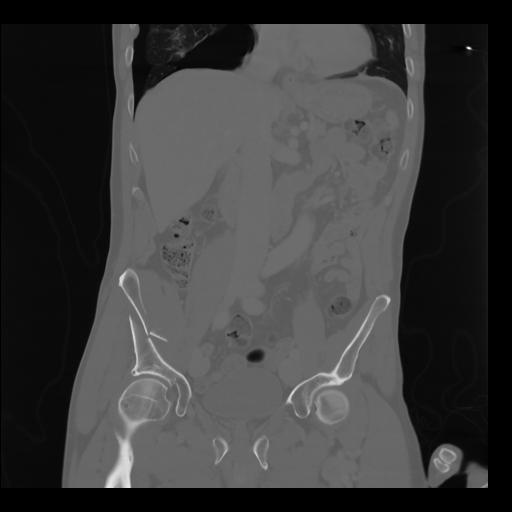

35 CUERPO,CE,Coronal,3.000,CUERPO,Coronal,